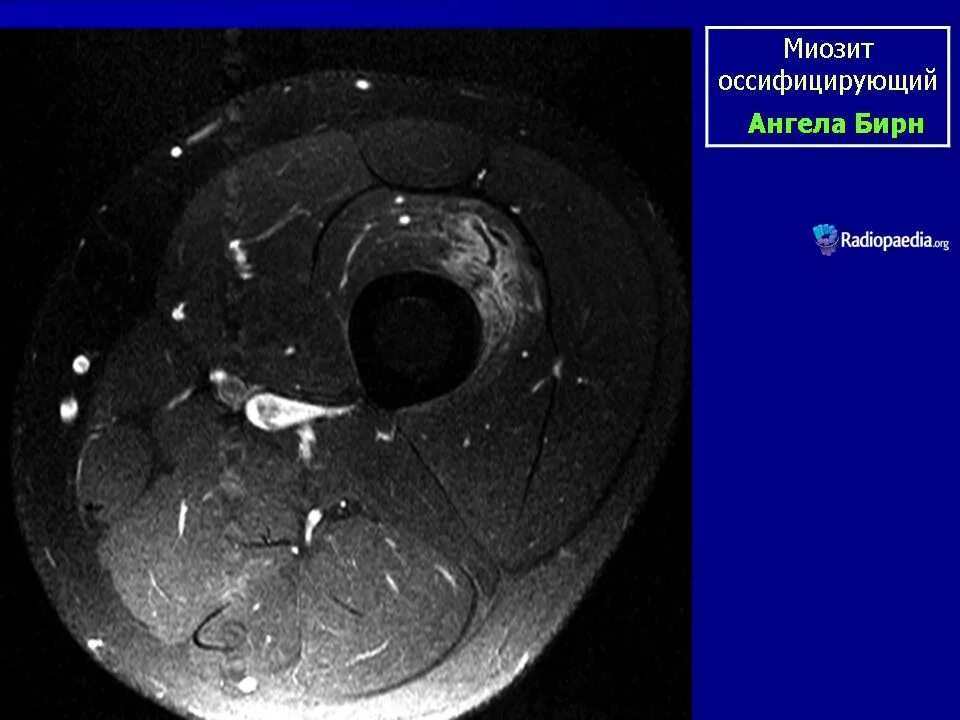

Оссифицированный миозит